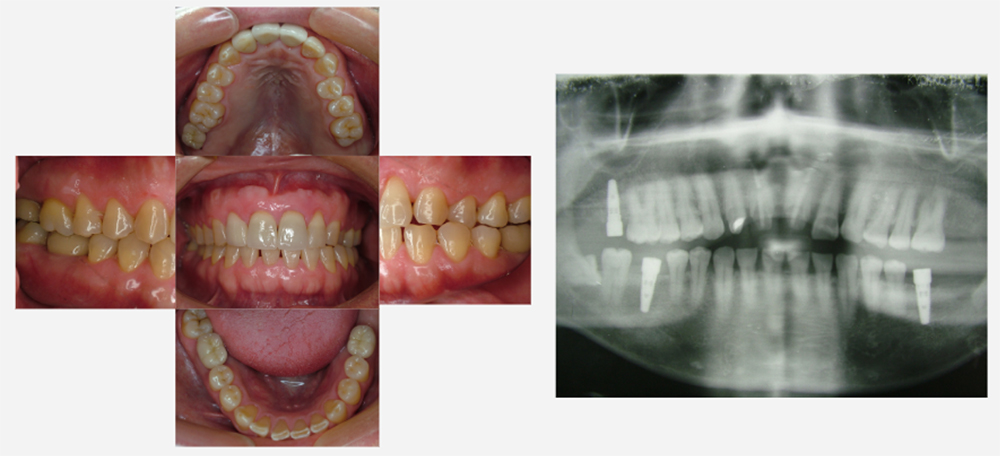

治療前治療後

| 治療内容 | インプラント奥歯1本・根管治療6歯 |

|---|---|

| 患者様の年齢 | 54歳 |

| 患者様の性別 | 女性 |

| 治療期間 | 2年 |

| 治療回数 | 根管治療合わせて70回程度 |

| 治療費用 | インプラント1歯 50万円/根管治療6歯 30万円 |